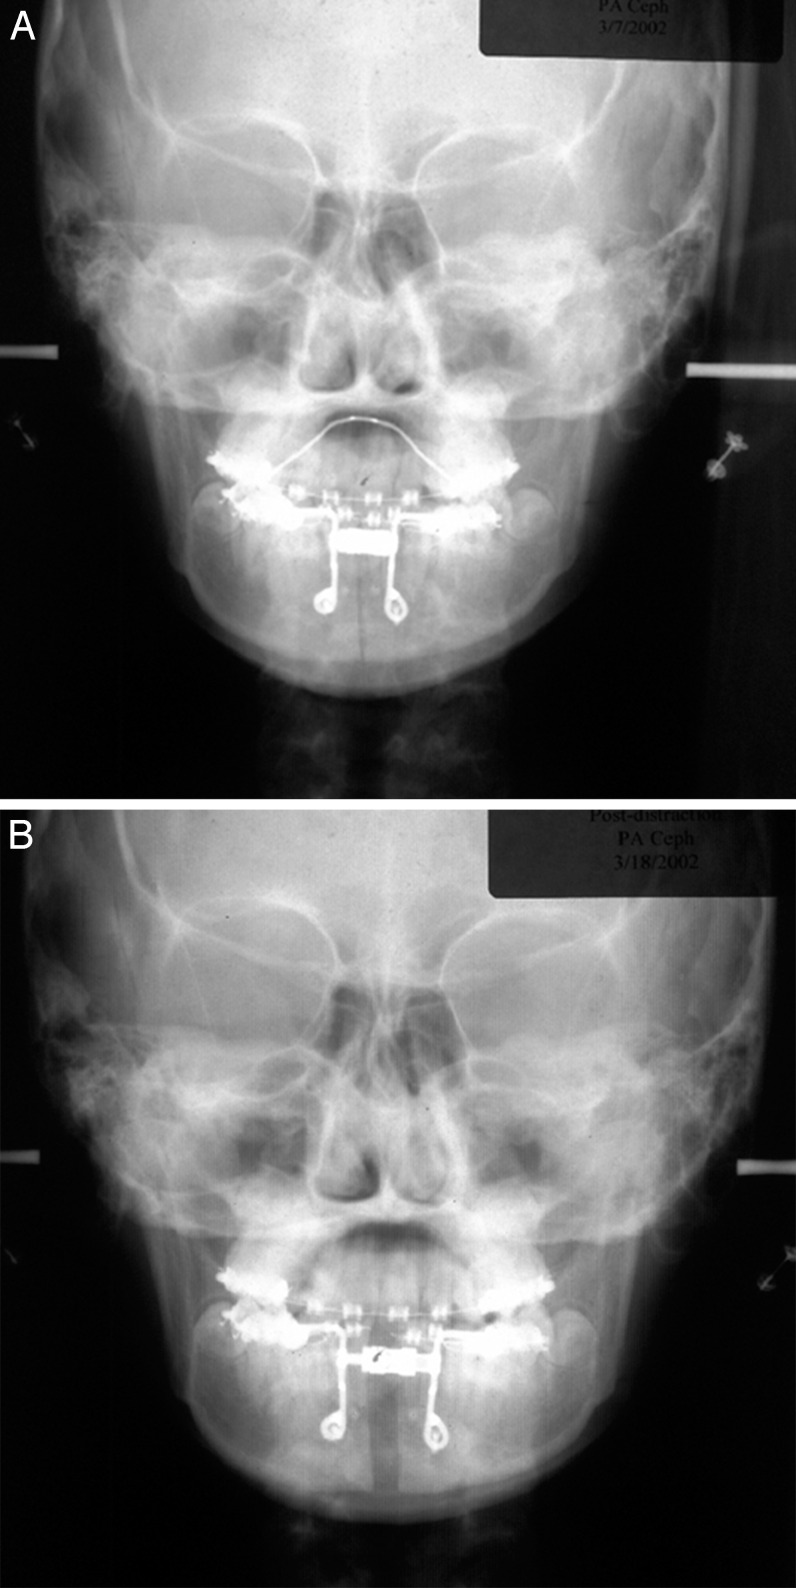

Just finished up this case and sent it to production.

-About 8mm right and 10mm left widening on jaws.

-Both sides of jaw about 4.5mm height added.

-Concavity to jaw shape added/fixed.

-Inframalars are 4.5mm and 5.5mm from 3/4 view.

-Fixed general asymmetries.

-3.1mm saddle.

-Infra rim shape has a slight, but improved, curve to keep a natural look.

There will be a genioplasty as well.

-About 8mm right and 10mm left widening on jaws.

-Both sides of jaw about 4.5mm height added.

-Concavity to jaw shape added/fixed.

-Inframalars are 4.5mm and 5.5mm from 3/4 view.

-Fixed general asymmetries.

-3.1mm saddle.

-Infra rim shape has a slight, but improved, curve to keep a natural look.

There will be a genioplasty as well.